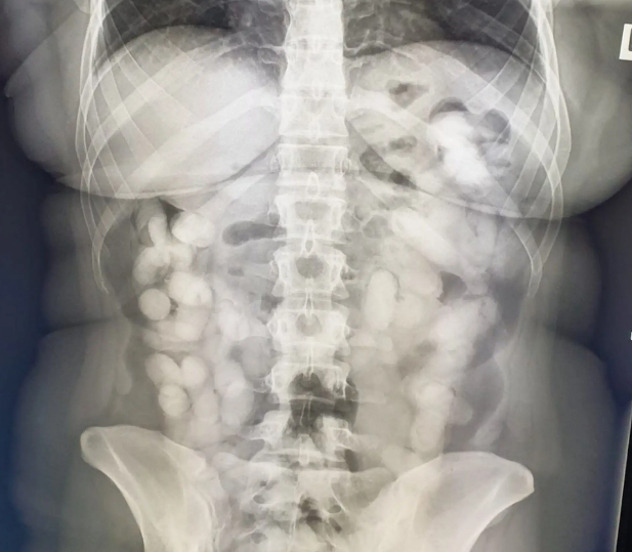

Nju su izdvojili od ostalih putnika, a pregledom je utvrđeno prisustvo droge na prtljagu. Nakon toga je upućena na rendgensko snimanje kojim je utvrđeno da u tijelu ima 76 stranih tijela, tj. kapsula.

Ono što je zanimljivo je to da je Andrei trebalo punih 10 dana da iz tijela "izbaci" kapsule s drogom, uprkos tome što je uzimala jake laksative. Nakon deset dana utvrđeno je da je ona u tijelu imala ukupno 990 grama kokaina.